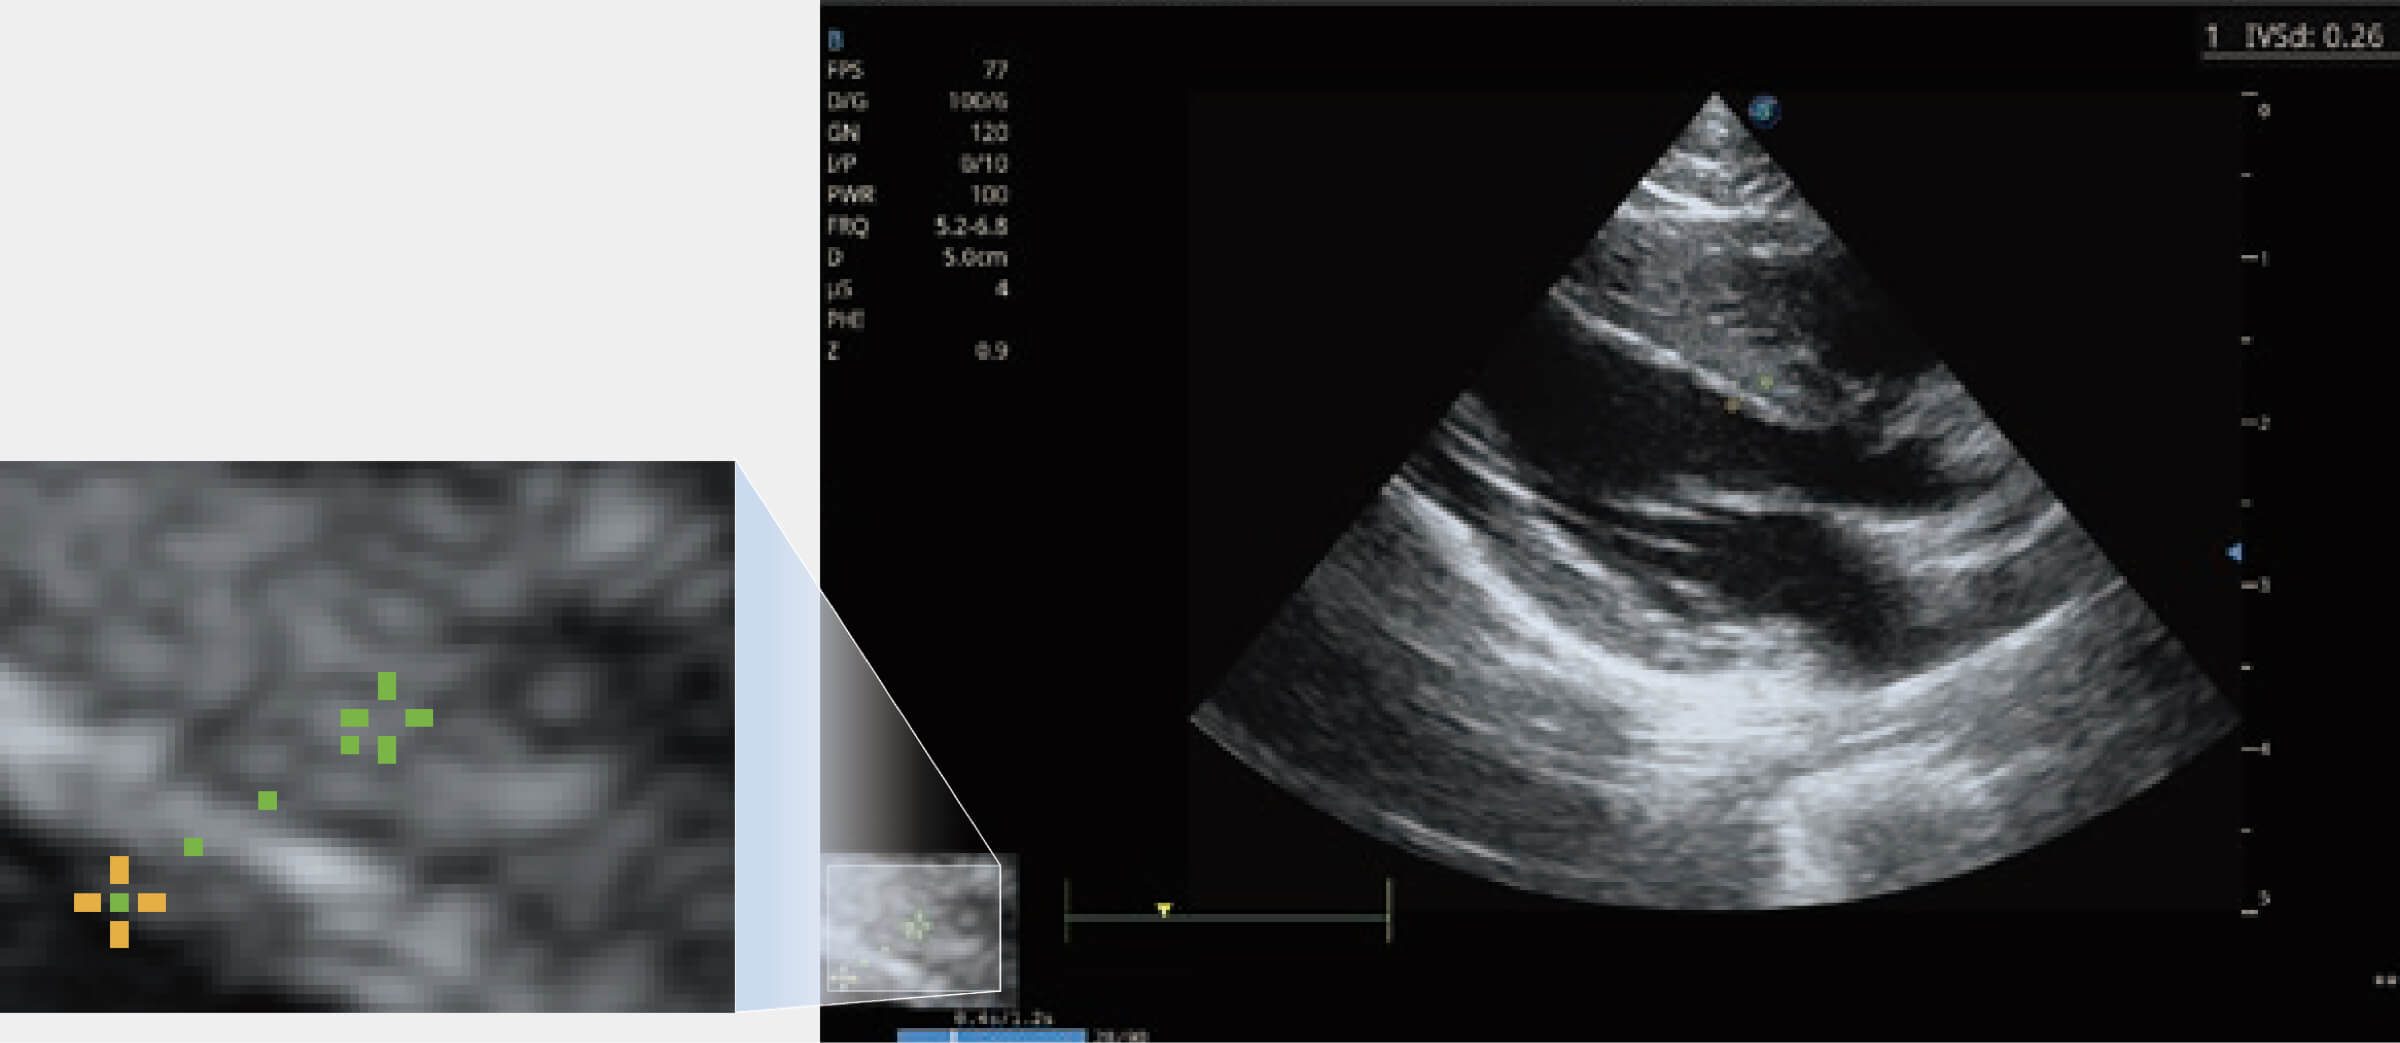

提供解剖示意圖、標(biāo)準(zhǔn)超聲圖像、掃查手法涂和操作者實時檢查圖像,指導(dǎo)操作者進(jìn)行標(biāo)準(zhǔn)切面的正確掃查。